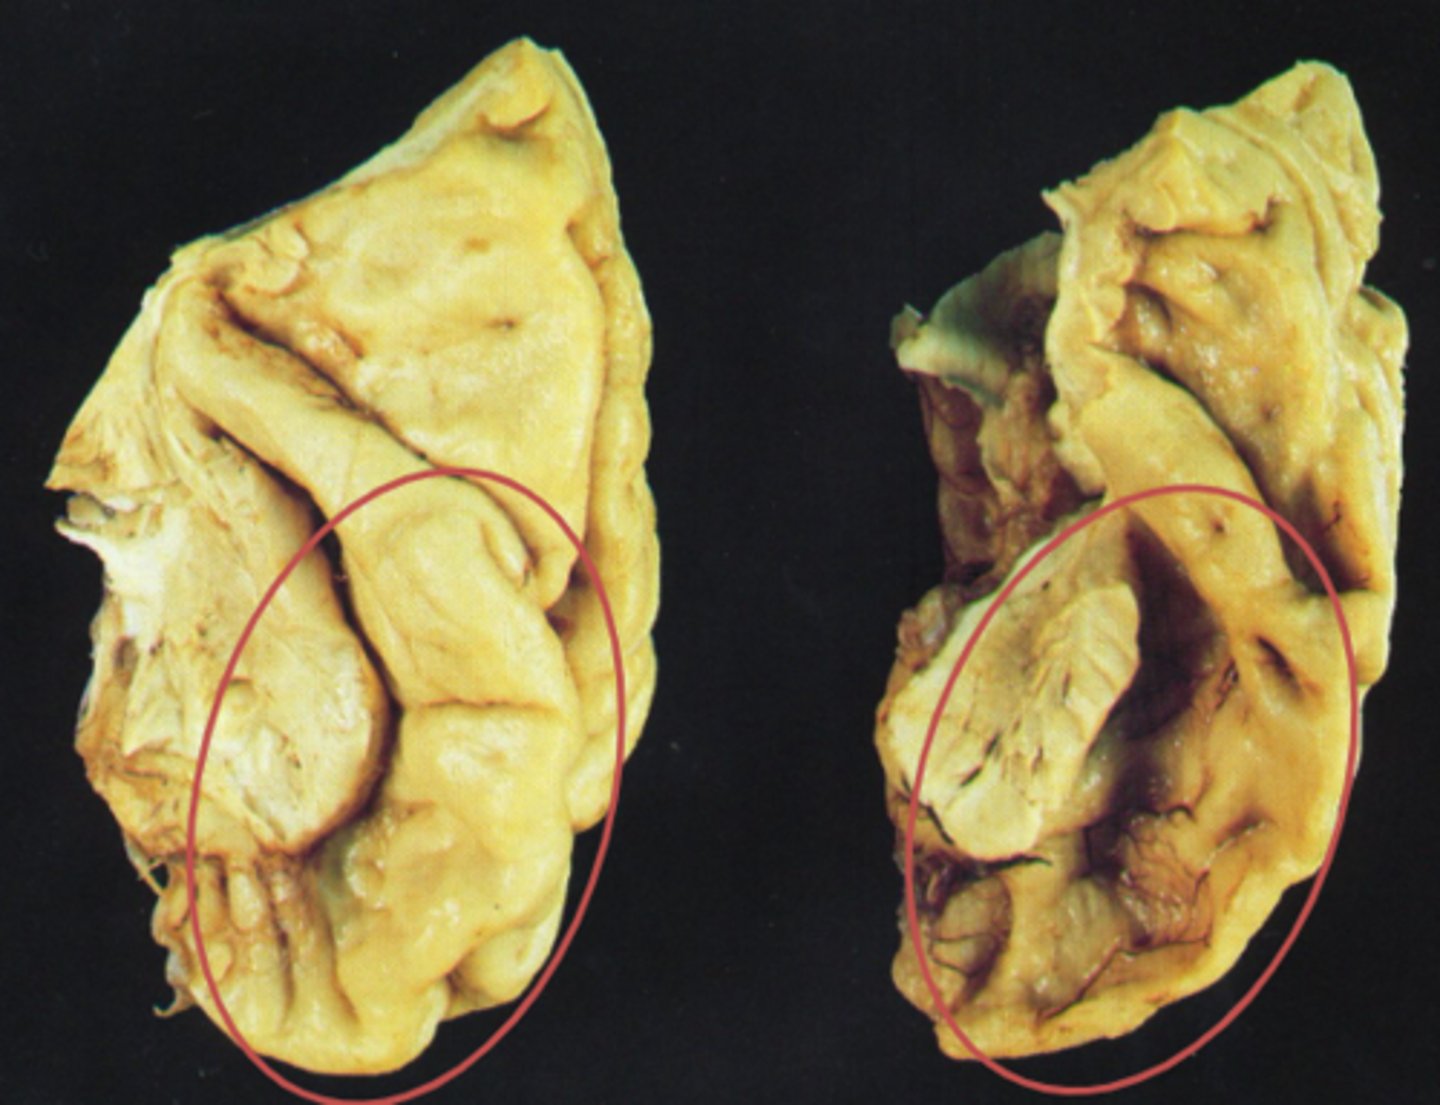

What is the etiology of fronto-temporal dementia (pick's disease)?

Build up of abnormal proteins (e.g. pick's bodies)

Atrophy of cortical regions of frontal and temporal lobes